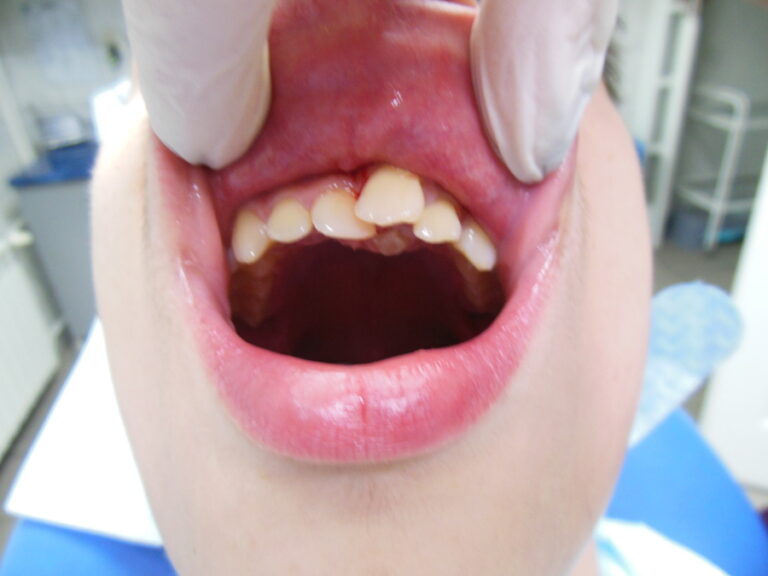

Przykłady implantologii

Zastosowanie implantoprotetyki w przypadku gdy klasyczna protetyka nie sprawdza się.